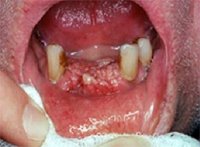

يعتبر سرطان اللثة من الانواع الخبيثة جدا، اذ يمكنه ان يسير بمرحلة خفية طويلة، خاصة ان كانت القرحات التي يسببها صغيرة في البداية من دون إحداث آلام، ويكتشفها طبيب الأسنان في بعض الأحيان خلال فحص روتيني لكامل الفم، أو بسبب شكوى المريض من التهابات دائمة في اللثة.

ويقول البروفسور الأميركي ان إجراء عملية الكشف بسيطة جدا، فبعد غسل المريض لفمه بمادة حادة كالخل مثلا من اجل ازالة كل ما علق بها، يغسل الفم بالسائل الكاشف وبعد دقائق قليلة يبصق السائل ويغسل فمه جيدا جدا ومن الأفضل ان يكون ذلك بمسحوق خاص لتنظيف الفم. فاذا اصبحت انسجة اللثة زرقاء فاتحة فهذه إشارة الى وجود التهاب، اما اذا كانت زرقاء داكنة جدا فهذا مؤشر لوجود بؤرة سرطانية، عندها على الطبيب المباشرة بالفحوصات والعلاجات اللازمة إذ يكون المرض في أول مراحله. ويضيف البروفسور، ان المادة الكاشفة لا تستخدم لتحري السرطان فحسب، وانما لديها قدرة على تقصي بؤر الالتهاب في الفم، وبالطبع يمكن تمييز الالتهابات عن السرطان من خلال درجة تكون النسيج.